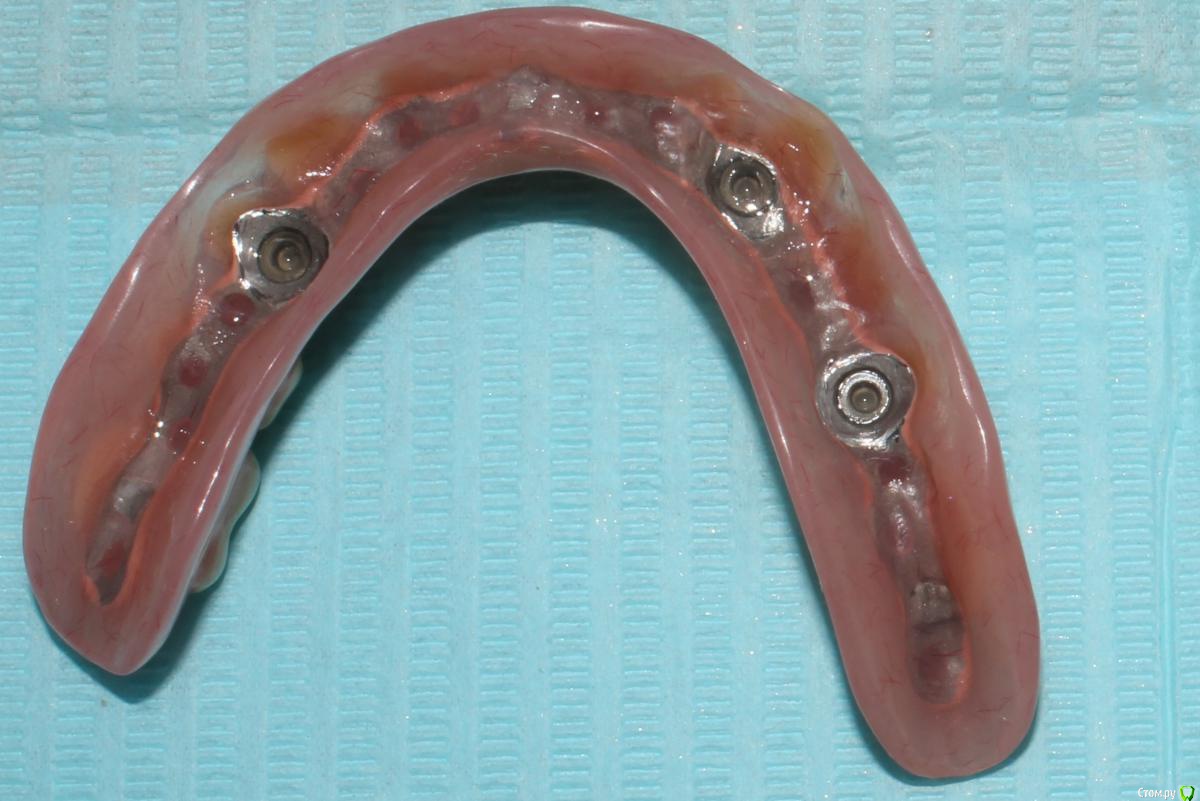

dr.Dre Опубликовано 1 февраля, 2016 Поделиться Опубликовано 1 февраля, 2016 Добрый день что это за система фиксации съёмников ? Ссылка на комментарий

Stomka Опубликовано 1 февраля, 2016 Поделиться Опубликовано 1 февраля, 2016 (изменено) я знаю, что это называется супрарадикулярный аттачмент.. по моему не тянет на громкое слово "система" Изменено 1 февраля, 2016 пользователем Stomka Ссылка на комментарий

Larnary Опубликовано 1 февраля, 2016 Поделиться Опубликовано 1 февраля, 2016 (изменено) Обычные Бреденты(или аналог) на вкладках. Реализация идеи ненадежная. Что касается протеза на нижнюю челюсть.Правильнее было бы сделать в протезе литую балку и вставить в нее матрицы. Изменено 1 февраля, 2016 пользователем Larnary Ссылка на комментарий

Ronin Опубликовано 1 февраля, 2016 Поделиться Опубликовано 1 февраля, 2016 У меня это просто культевые аттачменты по типу бредента, как упомянули ранее)) иногда приходится делать, когда финансы не позволяют разгуляться на другие виды конструкций или в свете атрофии и сопутствуещей патологии.. Зато лучше, чем просто съемник при диабете или частичный. А по поводу фиксации самих замков, то как вкладки, если нормально ставить, соблюдая протокол, то ничего не вылетает))) Ссылка на комментарий